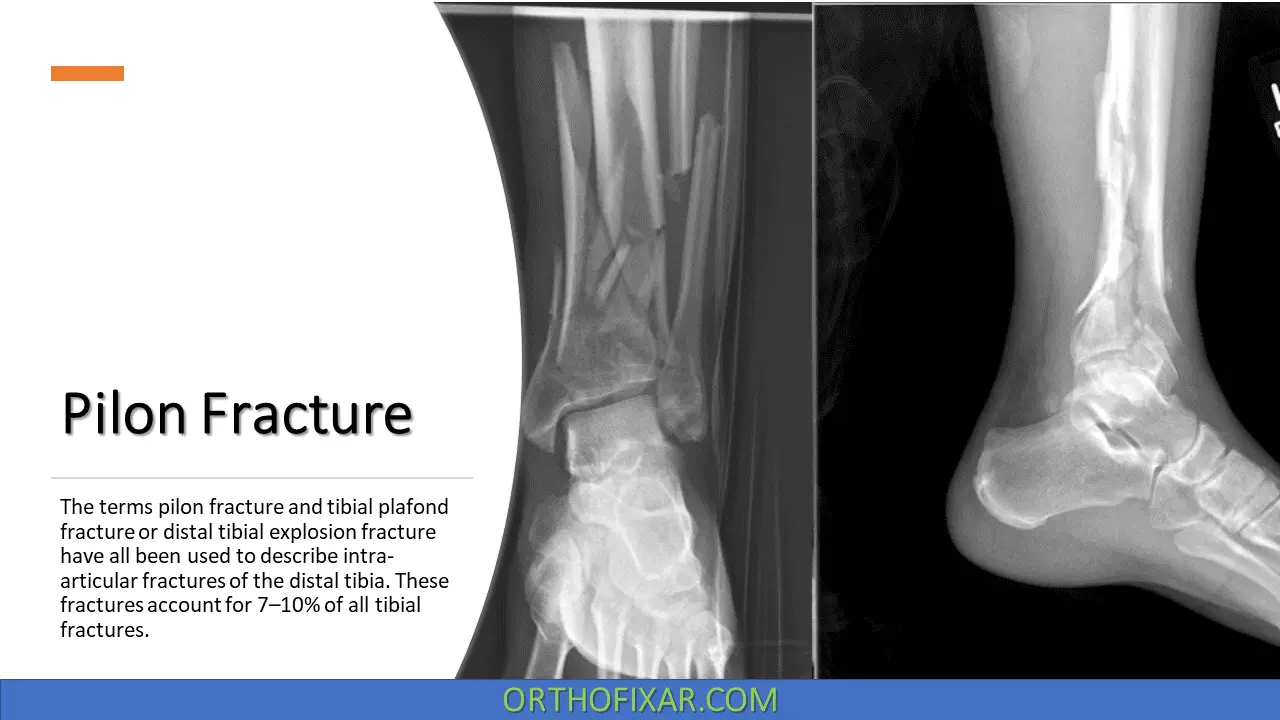

The terms pilon fracture, tibial plafond fracture or distal tibial fracture have all been used to describe intra-articular fractures of the distal tibia.

Pilon fractures mostly result from high-energy trauma such as motor vehicle accidents and falls from a height that causes direct axial compression. These fractures account for 7–10% of all tibial fractures.